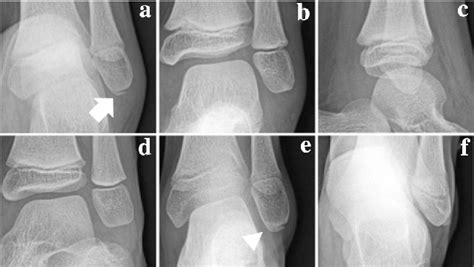

Proximal Tibia Fracture After Anterior Cruciate Ligament ...

Proximal Tibia Fracture After Anterior Cruciate Ligament ... from media.springernature.com

Without surgical intervention, a full recovery is not favourable. Torn anterior cruciate ligament (torn acl or acl injury). Without surgical intervention, a full recovery is not favourable. An avulsion fracture occurs when a tendon or ligament attached to a bone pulls against it and fractures off a piece of the bone. Torn acl recovery time all depends on what happened to your ligament and how it's treated. The most commonly torn ligament inside the knee is the anterior cruciate ligament (acl). There will be very little or no function of the knee. With a separation break, damage deep down happens close where the bone joins to a ligament or tendon. This typically involves separation of the tibial attachment of the acl to variable degrees. I think we can all agree that there's nothing better… The vdo demonstrate technique of the arthroscopic fixation acl avulsion fracture. Most often, this occurs during sudden movements and changes in direction. They usually happen when a bone is moving one way, and a tendon or most of the time, however, avulsion fractures do not require surgery. The classic signs/symptoms of acl rupture include pain and a popping sensation at the time of injury, immediate swelling and. This can occur at the ligament by the application of forces external to the body (such as a fall or pull). What is the typical treatment & recovery time for this injury? Acl avulsion fracture is the fracture of the tibial attachment of acl at the anterior intercondylar region.